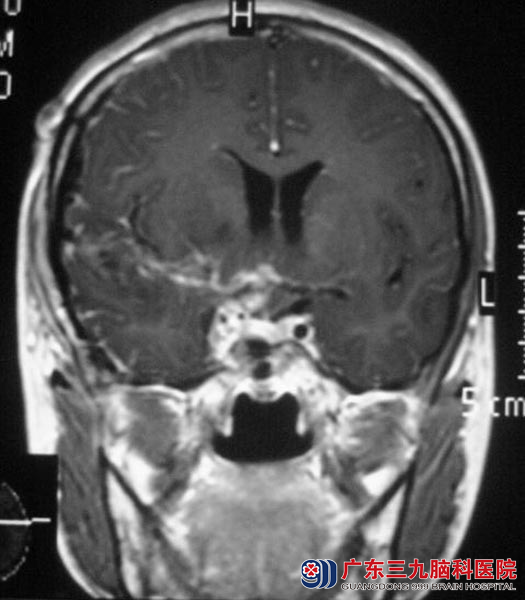

同学们开始帮着小惠找医院,经过不断的咨询,她们选择了广东三九脑科医院。头颅MR检查提示肿瘤大小约42.0mm×47.5mm×45.8mm,邻近脑室受压,三脑室明显受压变窄,右侧侧脑室受压,中线结构左偏。邻近视交叉右侧显示不清,右侧海绵窦部分边缘与病史分界不清。

由综合神经外科 鲁明主任主刀,在全麻下行肿瘤切除手术,硬膜血供较丰富,暴露中颅窝底,见灰白色肿瘤,质韧,有完整包膜,血供丰富,广基与蝶骨嵴及部分颞鳞部硬膜相连,与周围脑组织部分粘连易分离,显微镜下电凝肿瘤于颅底硬膜连接处,向前至前床突,前颅窝底后部,向后至岩斜区,超声吸引吸除部分肿瘤,分离与脑组织粘连肿瘤,边分离边分块切除,从前床突处分离肿瘤见颈内动脉,棉片保护血管,仔细分离出颈内动脉、大脑中动脉、大脑前动脉及视神经,切除分离的部分肿瘤,见肿瘤向海绵窦内侵犯,在显微镜下予肿瘤切除,达辛普森I级,手术对颈内动脉、大脑中动脉、大脑前动脉、视神经、动眼神经保护完整。小惠已康复出院。术后病理结果为:脑膜瘤(合体细胞型,WHO I级)。